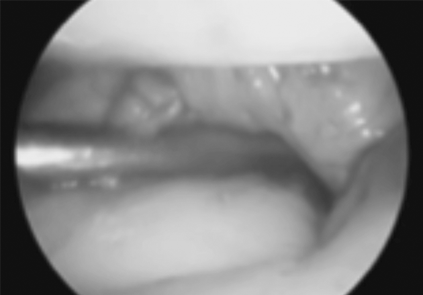

L’engruiximent i la constricció de la beina sinovial impedeix el lliscament fàcil dels tendons que flexionen els dits.